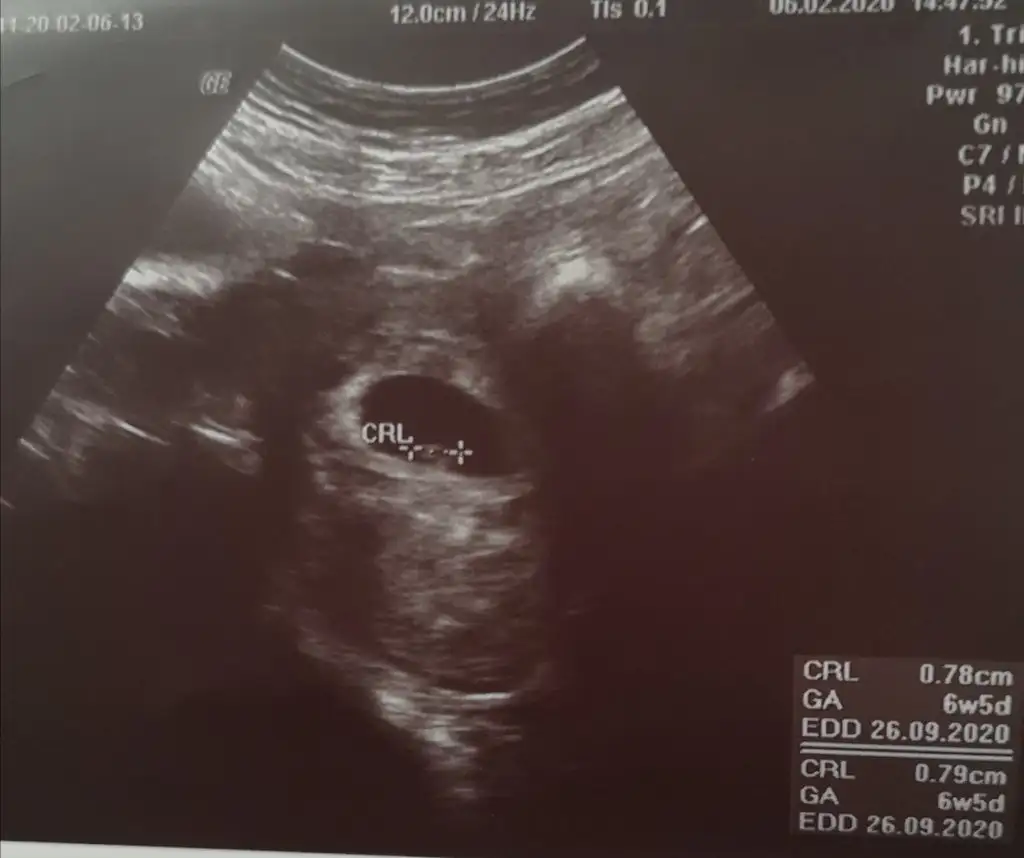

6 7 haftalık varsa atın yoksa 12 haftalık. Olunca atınBenimde sata gore 8+4 tu ama doktorum 9+3 dedi ondrn gidiyo uzun boylu olcsk dedi kese sekline gore yorumlayabiliyonuzmu yoksa 12.haftaninmi usg sini atmam gerekiyor

Buda 6+4 tu6 7 haftalık varsa atın yoksa 12 haftalık. Olunca atın

Buda 6+4 tu